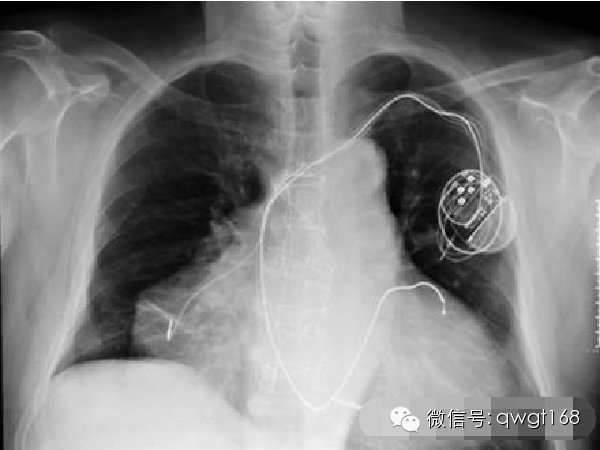

6. 拥有两个心脏并在双重心脏问题下存活的男人

2010年,起初这个病人并没有任何特殊的异常,他呼吸急促伴有血压偏低,毫无疑问这是心血管问题。急诊室的医生经常看到这种类似的症状。

医生们认为他患有典型的心脏骤停,直到他们做了更加细致的检查后才注意到他不同寻常的疾病。事实证明,这个男人并不是先天具有两个心脏,第二个心脏是在他进行早期医疗的时候出现在原心脏上的。

采用心脏异位移植会出现一对新的心脏,一个正常的和一个病变的。这当然也有内在风险,因为移植成功的话会出现两个独立的心律,但在这种情况下,一个心脏会更好一点。进了医院以后,医生对他进行了药物治疗,试图纠正他的节律障碍,并使用药物方法使他的两颗心脏停工,之后再用电击器使两颗心脏同时恢复功能。据报道,目前男子的两颗心脏都运作正常。